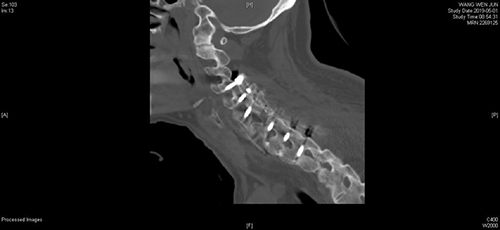

一切准备就绪后,脊柱外科专家们为患者实施了颈椎前后联合入路减压植骨融合内固定术。手术在患者全身麻醉后紧张有序地进行。强直性脊柱炎骨折脱位的患者,脊柱僵硬,由于骨质疏松,无法进行牵引下复位,且常规的侧块螺钉由于把持力小,也难以复位。专家团队首先从后路应用了难度较大椎弓根螺钉进行固定,顺利提拉复位,完成了解剖复位。解剖复位之后,改变患者体位,进行前路手术,在颈6-7椎间进行植骨融合,钛板固定。

手术前后影像学对照(术前C6双侧椎板骨折、C7椎体完全骨折脱位,术后达到解剖复位)

前后路联合手术,使患者颈椎的稳定性大大增加,术后早期就可以下地行走。经过全程监护和系统治疗,患者术后恢复良好,骨折解剖复位,复查X线及CT显示固定位置佳,术后3天即下地行走,术后4天即出院回家休养。